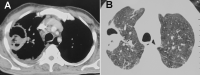

Severe coronavirus disease (COVID-19) is currently managed with systemic glucocorticoids. Opportunistic fungal infections are of concern in such patients. While COVID-19 associated pulmonary aspergillosis is increasingly recognized, mucormycosis is rare. We describe a case of probable pulmonary mucormycosis in a 55-year-old man with diabetes, end-stage kidney disease, and COVID-19. The index case was diagnosed with pulmonary mucormycosis 21 days following admission for severe COVID-19. He received 5 g of liposomal amphotericin B and was discharged after 54 days from the hospital. We also performed a systematic review of the literature and identified seven additional cases of COVID-19 associated mucormycosis (CAM). Of the eight cases included in our review, diabetes mellitus was the most common risk factor. Three subjects had no risk factor other than glucocorticoids for COVID-19. Mucormycosis usually developed 10-14 days after hospitalization. All except the index case died. In two subjects, CAM was diagnosed postmortem. Mucormycosis is an uncommon but serious infection that complicates the course of severe COVID-19. Subjects with diabetes mellitus and multiple risk factors may be at a higher risk for developing mucormycosis. Concurrent glucocorticoid therapy probably heightens the risk of mucormycosis. A high index of suspicion and aggressive management is required to improve outcomes.